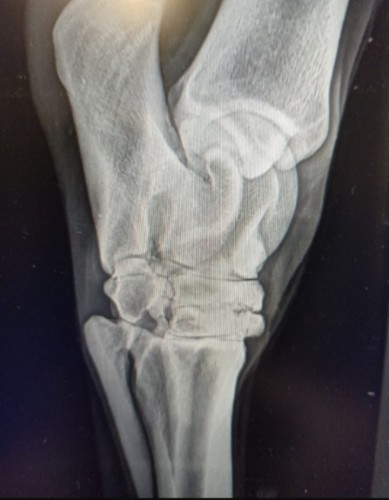

Anonymní: Dobrý den,mohu se prosím zeptat,rozumí tady někdo snímků z rtg. Konik prý má artrózou v zadní noze. Zajímalo by mě ,jak moc je ta artroza rozsáhlá. Budu ráda za názory

Chýva tam miestami kĺbna štrbina - takže závažná je celkom dosť (nie som ortopéd), ale to je iba snímok, neliečime snímok, ale zviera- teda snímky (hocaké výsledky) vždy v kontexte ako kôň vyzerá, koľko má rokov, ako chodí, načo ho chcete využívať a čo viete /chcete /môžte-neviete /nechcete /nemôžte poskytnúť.

Horsana:Chýva tam miestami kĺbna štrbina - takže závažná je celkom dosť (nie som ortopéd), ale to je iba snímok, neliečime snímok, ale zviera- teda snímky (hocaké výsledky) vždy v kontexte ako kôň vyzerá, koľko má rokov, ako chodí, načo ho chcete využívať a čo viete /chcete /môžte-neviete /nechcete /nemôžte poskytnúť.